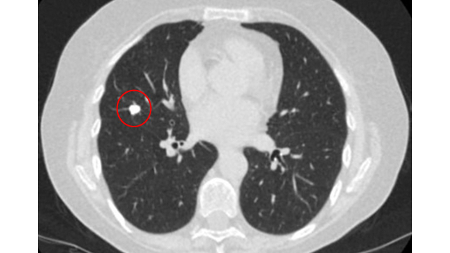

Computed tomography (CT) showing examples of malignant perifissural nodules. Note the spiculated edge of the nodules and the evident retraction of the adjacent fissure. Both resection tissue analyses confirmed adenocarcinoma of lung

From the collection of Dr George Tsaknis, MD, PhD, FRCP(London), MRQA, MAcadMEd, PGCert; used with permission